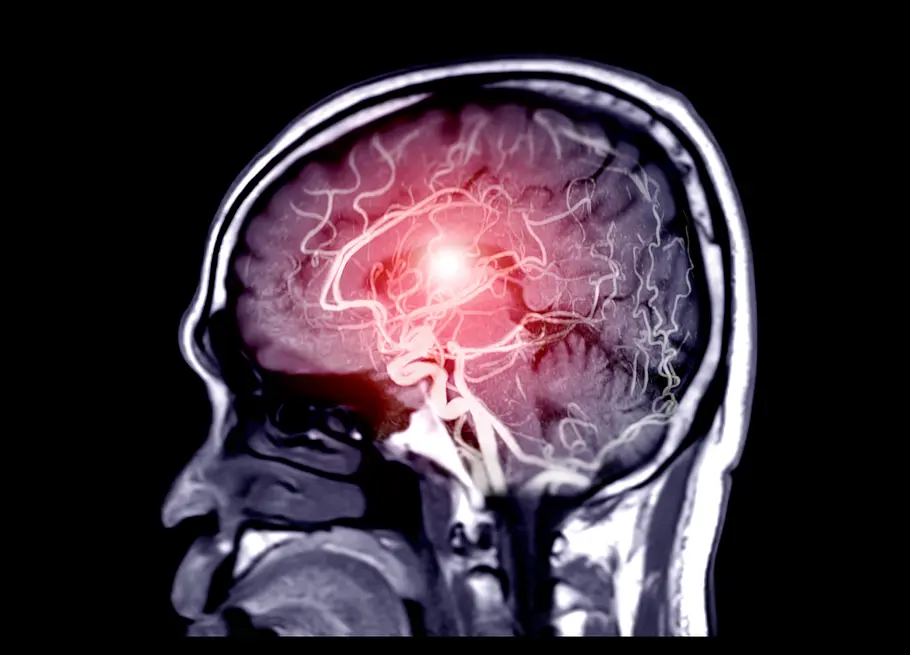

Aphasie ist der altgriechische Begriff für "Sprachlosigkeit". Eine Aphasie wird in der medizinischen Fachsprache eine Sprachstörung genannt, die als Folge einer Krankheit auftritt. In den meisten Fällen (ca. 80%) ist ein Schlaganfall der Grund für die Aphasie. Weitere Gründe können Blutungen nach Venenthrombosen, ein Schädel-Hirn-Trauma, ein Gehirntumor, eine entzündliche Erkrankung, Sauerstoffmangel (Hypoxie) oder auch eine Vergiftung sein.